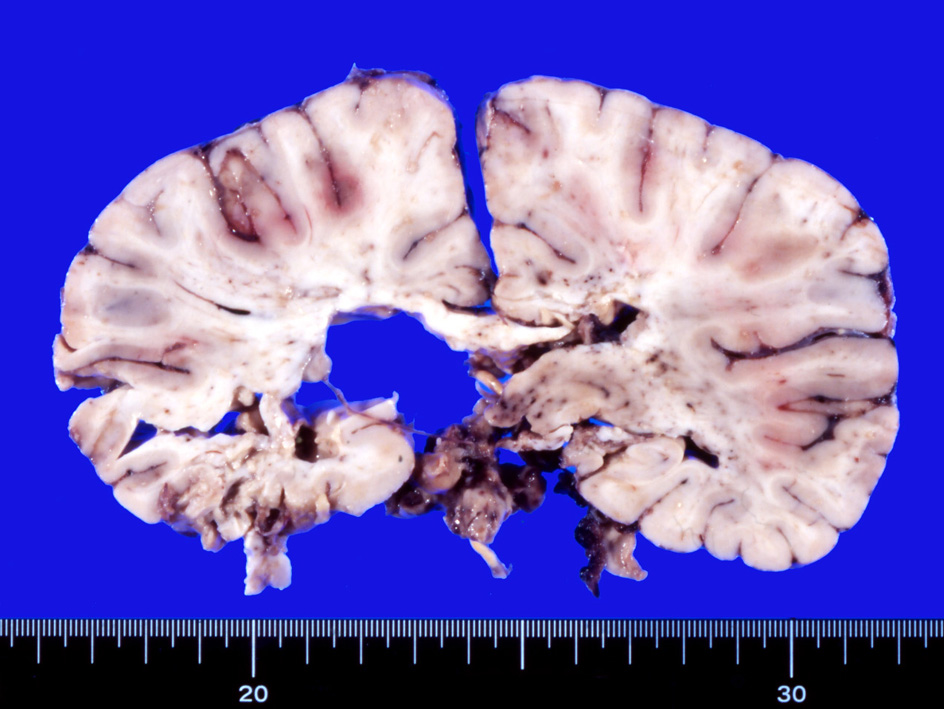

剖検肉眼病理所見

多発脳梗塞, 点在する出血壊死, 壊死に陥った組織が欠落している。